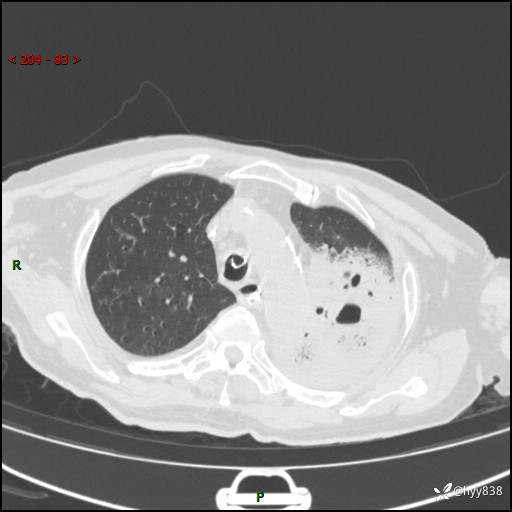

胸部CT复查(2024.8.5)